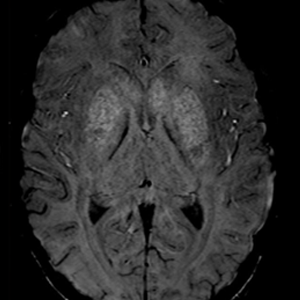

Caso 1 | Abril 2026 | Instituto Oulton

Motivo de consulta: cuadro progresivo de desorientación, apatía, bradipsiquia y disartria, seguido de un episodio de pérdida de conocimiento.